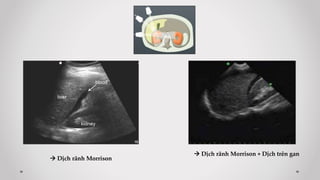

 Mặt cắt 2: liên sườn Phải

Trả lời các câu hỏi:

- Có dịch rãnh gan-thận (Morrison)?

- Chấn thương gan (P)? Thận (P)?

 Dịch rãnh Morrison

 Dịch rãnh Morrison + Dịch trên gan